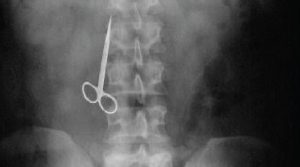

Medicina legale – Risarcimento del danno per colpa medica

Gli studi Medici Arcangeli, svolgono attività di consulenza tra il nesso casuale tra l’operato del sanitario e l’eventuale danno arrecato al suo assistito.